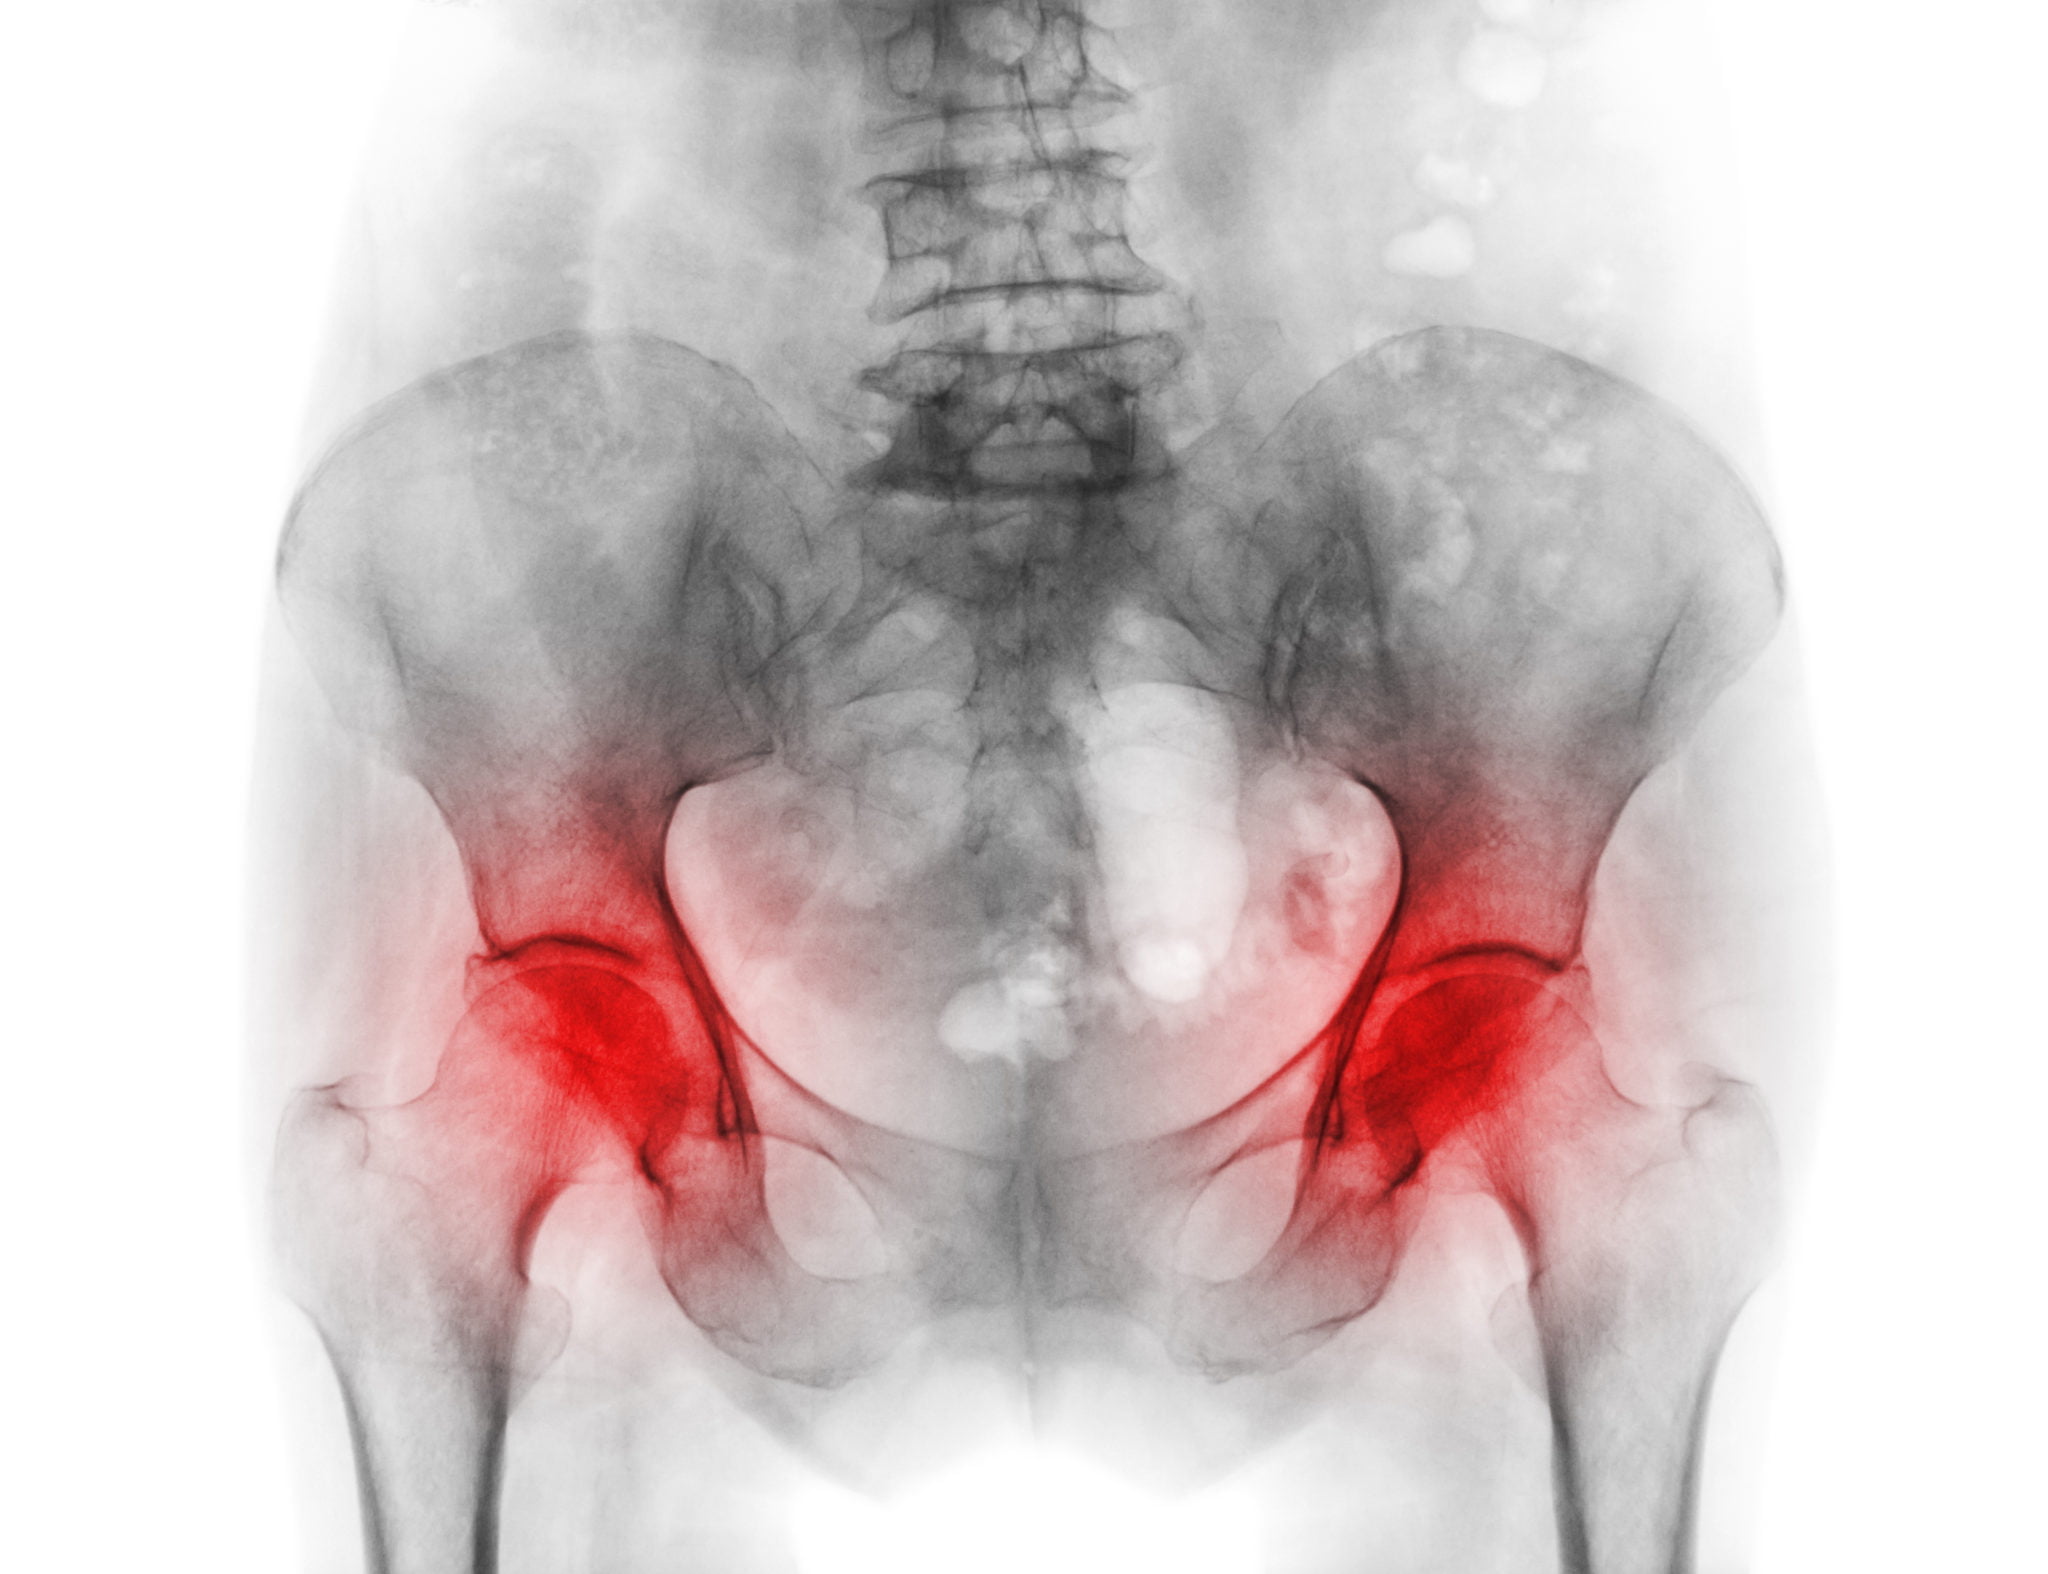

Une douleur à la hanche peut être due à plusieurs causes. Celles-ci peuvent être classées en problèmes de hanche primaires, secondaires, et douleur référée. La douleur de la hanche primaire peut être due à des déchirures labrales, une FAI, une hanche à ressaut, une synovite, une arthrite, des corps flottants, ou d’autres causes. Les problèmes de hanche secondaires incluent l’instabilité (anomalie du tissu conjonctif, dysplasie), la bursite, et le syndrome piriforme entre autres. La douleur référée peut venir entre autres du bas du dos, de l’articulation sacro-iliaque, d’un déséquilibre musculaire. Le traitement de la douleur de la hanche dépend de la cause primaire.

Arthrite inflammatoire – Hanche

L’œdème et la chaleur (inflammation) du revêtement articulaire appelé synovium entraine une libération d’enzymes qui ramollissent et détruisent éventuellement le cartilage. L’arthrite rhumatoïde, le lupus et l’arthrite psoriasique sont de nature inflammatoire.